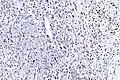

Histologically, epithelioid sarcoma forms nodules with central necrosis surrounded by bland, polygonal cells with eosinophilic cytoplasm and peripheral spindling.[3] Epithelioid sarcomas typically express vimentin, cytokeratins, epithelial membrane antigen, and CD34, whereas they are usually negative for S100, desmin, and FLI1 (FLI-1).[3] They characteristically lack the protein INI1 (see below). Epithelioid sarcomas typically stain positive for CA125.[4]

The most common genetic mutation (found in 80-90% of epithelioid sarcomas) is the inactivation of the SMARCB1 gene, or the loss of protein INI1 function,.[10][11] Epithelioid sarcoma typically contains chromosome 22q11.2 mutations or deletions and 8q gains. Aberrations of 18q as well as recurrent gains at 11q13, have also been observed.[12][13][14]

Tissue biopsy is the diagnostic modality of choice. Due to a high incidence of lymph node involvement, a sentinel lymph node biopsy may be performed. A common characteristic of epithelioid sarcoma (observed in 80% of all cases) is the loss of function of the SMARCB1 gene (whose protein product is termed BAF47, INI1, or hSNF5). Immunohistochemical staining of INI1 is available and helps to diagnose of epithelioid sarcoma. MRI is the diagnostic modality of choice for imaging prior to biopsy and pathologic diagnosis for most patients.

High mag. High mag. (SMARCB1)

High mag. (SMARCB1)